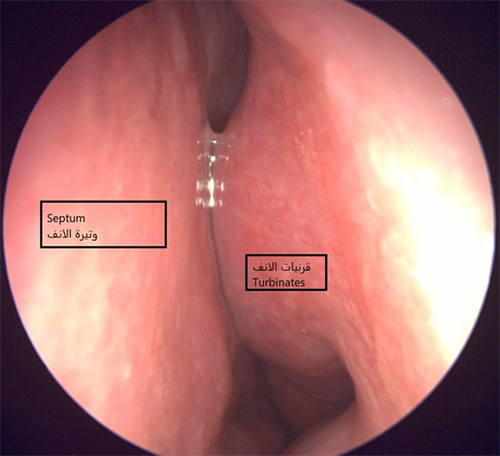

كيف يتم إجراء جراحة الجيوب الأنفية بالمنظار(FESS)؟

يتم ذلك من داخل الأنف ، باستخدام المنظار دون جروح خارجية.